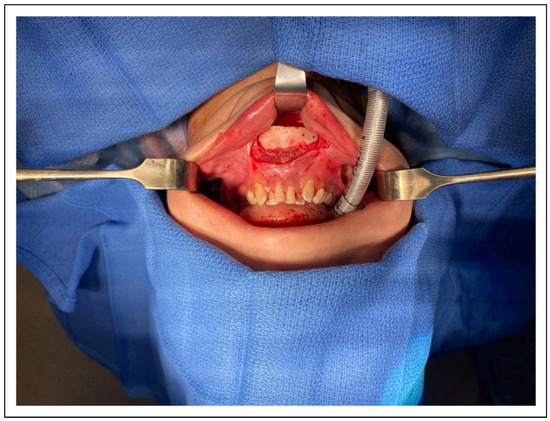

The approach to the jaw and chin uses a triple incision approach as described by the facial team [7] [Figure 10]. P# At the level of the gonial angle release of masseteric attachments by means of a long bovie tip can be helpful. P# Except for the masseteric attachments it is prudent to keep the periosteal sleeve intact as it reduces swelling and risk of traction injury of the marginal mandibular nerve. In our early experience we bent an oscillating 9 × 35 × 0.64 mm sawblade. However, the cut was not predictable and the visualization poor. The piezo attachments for the Synthes Piezoelectric system (Oberdorf, Switzerland) barely reached and only effectively performed a unicortical cut. Because of these technical limitations we only performed gonial angle resections in very select few patients. The other possibility drawn from orthognathic surgery is a vertical excision of the gonial angle using a reciprocating saw. Due to fear of injury to the inferior alveolar nerve and/or retromandibular vascular structures we have not used this technique. P# To circumvent the main 2 issues of 1) visibility and 2) perpendicular angle of the sawblade we started threading a Stryker micro-reciprocating sawblade (Kalamazoo, Michigan) retrograde through a trocar with subsequent removal of the trocar. This allows for excellent visualization [Figure 11]. To avoid any thermal injuries of the soft tissue we continuously irrigate the external skin with cold irrigation fluid. This approach also would lend itself to the use of VSP including cutting guides. Because the reciprocating saw is not protected by a trocar, care must be exercised to not pull the saw blade into the soft tissues with risk of inadvertent injury to the marginal mandibular nerve. The external incision can also be used for neck liposuction. By implementing this relatively simple approach to the gonial angle our threshold for offering gonial angle resection in patients who would benefit has significantly lowered and our outcomes for jawline feminization and reproducibility thereof increased [Figure 10 and Figure 11].

Figure 10.

Triple approach to jaw and chin feminization surgery. Note mucosal bridge between the access to the gonial angle and the chin.

Figure 11.

View of gonial angle with transbuccal reciprocating saw in the view.